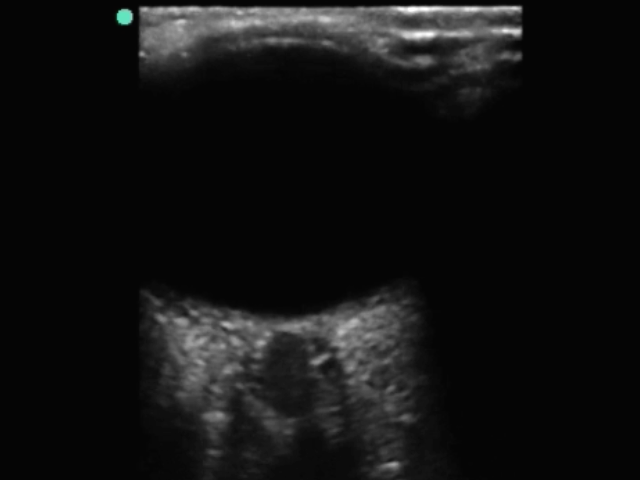

眼部视神经鞘 2 图像